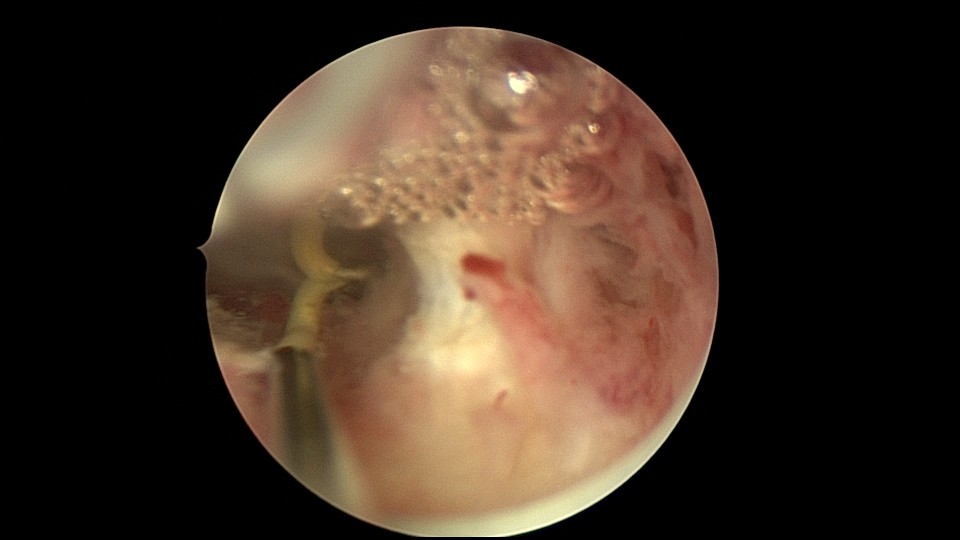

患者26岁,G7P1,剖宫产1次。2019年10月药流不全,行清宫术,术后闭经半年,后月经紊乱,周期28天~60天,月经量少。2021年4月,闭经50+天,B超提示宫腔粘连,宫腔镜见宫颈管上段封闭粘连,宫腔广泛粘连,AFS评12分(最高分)。宫腔镜电切分粘,恢复宫腔形态,显露双侧输卵管开口,宫腔防粘连复发处理,2021年5月宫腔镜二探取球囊。2021年7月自然妊娠,门诊人流并安环。2021年9月,月经推迟,B超提示宫腔粘连,节育环嵌顿,行宫腔镜取环并分粘,2021年10月二探取球囊。2021年12月放置皮埋避孕,2022年3月要求取出皮埋棒。2023年8月初自然妊娠,药流不全,2023年8月底行宫腔镜清除残留胚物。2024年2月自然妊娠10周,2024年4月初妊娠3+月(BPD2.6cm),坚决要求终止妊娠,行宫腔镜辅助终止妊娠。2025年6月因异常子宫出血再次宫腔镜分粘,2025年7月二探取球囊。现31岁,G10P1,前后共做了8次宫腔镜,术后多次自然妊娠,患者妊娠中途均选择了终止妊娠。